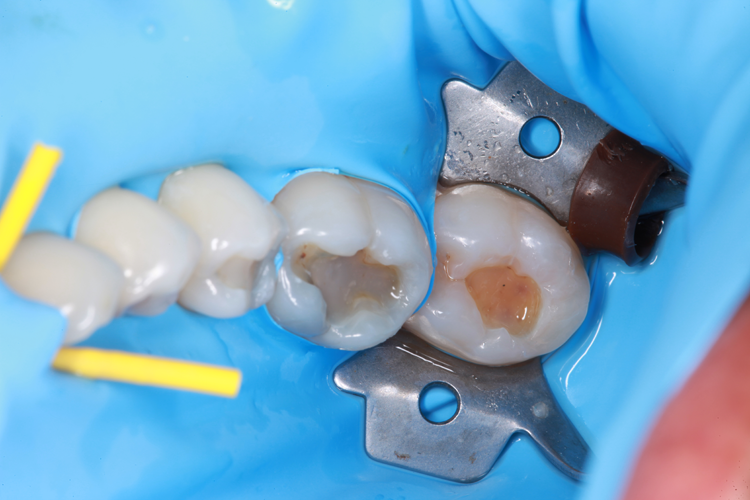

Technically, the procedure was very efficient. After the placement of rubber dam, the amalgam restorations (Fig. 1) and any signs of caries were removed (Fig. 2).

Fig. 1: Failed amalgam restoration. Fig. 2: Amalgam and decay are removed and tooth is prepared with ACTIVA BioACTIVE-RESTORATIVE.

The enamel was etched for 20 seconds with Select HV from BISCO (Fig. 3), and ALL-BOND UNIVERSAL (BISCO) was applied (Fig. 4).

Fig. 3: Enamel etched for 20 seconds with Select HV. Fig. 4: ALL-BOND UNIVERSAL applied.

The same procedure was followed for the remaining eight restorations. Figure 7 shows several posterior teeth prepared for restoration and enamel etched with Select HV (BISCO) for 20 seconds (Fig. 8). Figure 9 shows the final restorations.

Fig. 7 Amalgam and decay are removed and tooth is prepared with ACTIVA BioACTIVE-RESTORATIVE. Fig. 8: Enamel etched for 20 seconds with Select HV